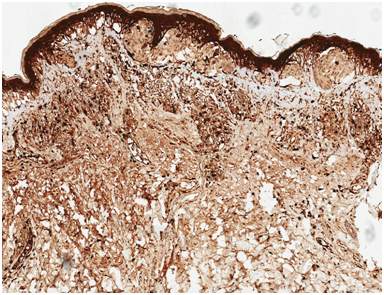

Following institutional review board-authorization, 13 primary cutaneous melanomas and 19 nevi were retrieved (5 common nevi, 5 mild dysplastic, 4 moderate dysplastic, and 5 severe dysplastic), (Figures 1-3). 5-μm formalin-fixed, paraffin-embedded sections were cut and mounted onto positively charged slides. Single IHC S100A9 staining was performed using the Leica Bond III protocol. All antibodies were purchased from Leica Biosystems (Buffalo Grove, IL). A board certified dermatopathologist evaluated S100A9 staining of melanocytes and keratinocytes in the epidermis of each sample. The pattern of staining was classified according to one of three categories: diffuse epidermal staining Figure 4, linear basement membrane staining Figure 5, and irregular patchy epidermal staining Figure 6.

Figure 4 Diffuse epidermal S100A9 stain of malignant melanoma in situ of lesion A.

The S100A9 protein, Calprotectin, is a protein that forms heterodimer within cells of myelomonocytic origin. With the exception of some epithelial tissue, S100A9 expression is found at low levels in healthy individuals and rises in response to epidermal injury in acute and chronic inflammation, UV exposure, tape stripping, and other skin stresses.3 The homodimer functions as a sensor and regulator of migration, proliferation, and differentiation of inflammatory cells.4 Experimental data indicate that a positive feedback mechanism, initiated and regulated by S100A9, is responsible for the inflammatory environment seen in many pathologic conditions (e.g. rheumatoid arthritis, systemic lupus erythematosus, giant cell arteritis, psoriasis, inflammatory bowel disease, and multiple sclerosis).5 During inflammation, myeloid cells promote an increase in intracellular calcium, resulting in the translocation of S100A9 to the membrane surface. The expression of S100A9 enhances leukocyte recruitment.5 This positive feedback mechanism ensures an aggressive inflammatory environment for successful tumor proliferation and metastases.6 In our study, the majority of non-worrisome nevi (compound nevi, mildly dysplastic nevi, moderately dysplastic nevi) stained primarily in an irregular pattern, severely dysplastic nevi stained a linear pattern (Figure 5), and the majority of melanoma lesions stained in a diffuse epidermal pattern. The dysplastic nevi did not appear to show increased levels of diffuse staining with grading of atypia. As severely dysplastic nevi could be histologically confused for melanoma and vice versa, a difference in staining pattern between severely dysplastic nevi and melanoma could be of clinical utility. From our results, a diffuse pattern would be more compatible with melanoma while a linear pattern would be more compatible with a severely dysplastic nevus. Hibino et al. reported diffuse staining of S100A9 in the epidermis overlying the melanoma and in the neighboring the epidermis. Additionally, the pigmented nevi in their study did not show significant S100A9 stain in the epidermis, and was similar to the irregular staining pattern we observed in our samples of benign nevi. Both of these findings correlate well with the results of our study.

We found that the depth of invasion in diffusely staining melanoma lesions was >1mm. Diffuse staining with S100A9 is correlated with a deeper invasion of the dermis by malignant cells. Heavy staining with S100A9 stain in melanoma lesions may support the “concentration effect” hypothesis of S100A9 function that higher levels of S100A9 may be correlated with increased tumor burden.7 In conclusion, the diffuse staining pattern of S100A9, although specific, is not highly sensitive. Due to our low sample size and lack of statistical significance, future research should investigate whether this marker has utility when diagnosing ambiguous lesions. Stratification into specific staining patterns with a greater number of samples may show that S100A9 has clinical use in both diagnosis and prognosis of malignant melanoma.